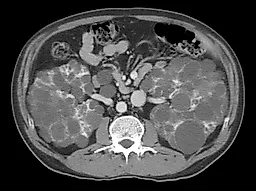

При подозрении на снижение почечного кровотока изотопнаяренография помогает уточнить степень нарушения кровоснабжения, а также выявить различия в кровоснабжении двух почек. Если требуется более специфическая анатомическая информация, почечная артериограмма и (или) почечная венограмма позволят точно определить наличие стеноза, окклюзированных участков почечных сосудов, аневризм и т. д. При подозрении на постренальную обструкцию полезно выполнение экскреторной урографии или ультразвукового исследования почек. В большинстве случаев этими методами можно выявить наличие гидронефроза. Более точная анатомическая информация может быть получена при КТ и МРИ органов брюшной полости и таза.